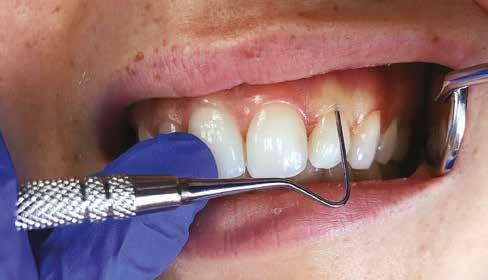

nak megfelelően – előkészítjük (orthofoszforsavval történő savazás, lemosás, szárítás és bond réteggel történő fedés). Ezzel egyidejűleg a ragasztásra kerülő héjak is előkészítésre kerülnek (hidrofolysavval történő savazás, lemosás, szárítás, szilanizálás, bond réteggel történő fedés, és végül az alkalmazni kívánt ragasztóanyag felvitele). Ezután a héjakat a fogak felszínén egyesével pozicionáljuk, majd néhány másodpercen keresztül polimerizációs lámpa segítségével megvilágítjuk. Ezt követően a kifolyó ragasztófelesleget eltávolítjuk, majd elvégezzük a restaurátumok végső polimerizálását. A héjak végleges rögzítését követően az esetlegesen visszamaradt ragasztómaradványok eltávolításra kerülnek, valamint ellenőrizzük az okklúzió és artikuláció közben létrejövő fogérintkezéseket. Az optimális esztétikai eredmény biztosítása érdekében kiemelt jelentősége van a papillák helyreállításának (rózsaszín esztétika). A modern fogorvoslás egyik kiemelt célja a fehér- és rózsaszín esztétika közti harmonikus egyensúly megteremtése. A papillák színe, nagysága és szimmetrikus megjelenése meghatározó szerepet tölt be a rózsaszín esztétika kialakításában. Az íny lefutása ugyancsak rendkívül jelentős mértékben befolyásolja a páciens fogazatának esztétikus megjelenését.

Manapság egyre gyakrabban találkozhatunk olyan páciensekkel, akik már a kezelések megkezdése előtt informálódnak a számukra elérhető kezelésekről, és ennek megfelelően jól definiált igényekkel érkeznek a rendelőnkbe. A páciensekkel történő megbeszélések során nagyon fontos, hogy részletesen felvilágosítsuk őket az általuk preferált kezelések előnyeiről és esetleges hátrányairól, valamint szintén

előnyös, ha egyéb terápiás alternatívákat is tudunk kínálni számukra.